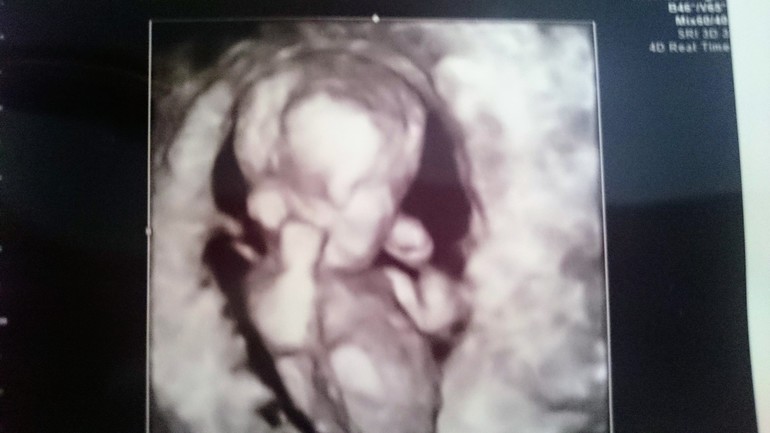

1 скрининг пройден

Девочки, как я счаслива! Омфалоцеле ушло,животик ровненький. Все у нас в норме, сердечко 156 ударов, все замерили, пальчики посчитали. Скорее всего у нас девчушка 😊 98 %. Я так рада. Боженька значит мне малышку послал, папа у нас мальчика ждал))) говорит, ещё в один декрет пойдёшь?)))))

Поздравляю!главное малыш здоровый,а кто там думаю не так важно.Пойдете потом за сыночком.Вы в 4д узи были?